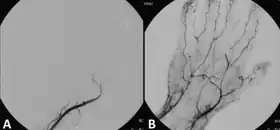

Angiograph before and after thrombolytic therapy in a case of acute limb ischemia. | |